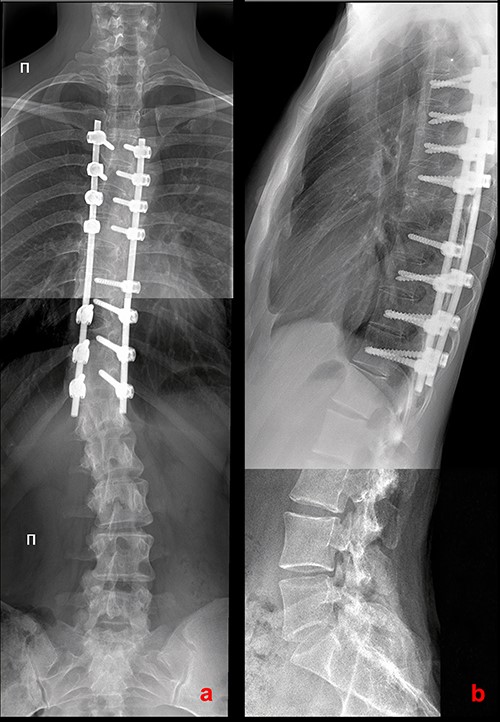

On 10-year follow-up, radiographs of the spine in the standing position in 2021 adequate correction are preserved with a slight asymptomatic increase of lumbar deformity (Figs 4 and 5).

X-rays of the patient’s spine at a 10-year follow-up. (a) AP X-ray of the spine in standing position. There is a slight increase in the lumbar curve. (b) Lateral X-ray of the spine in standing position.